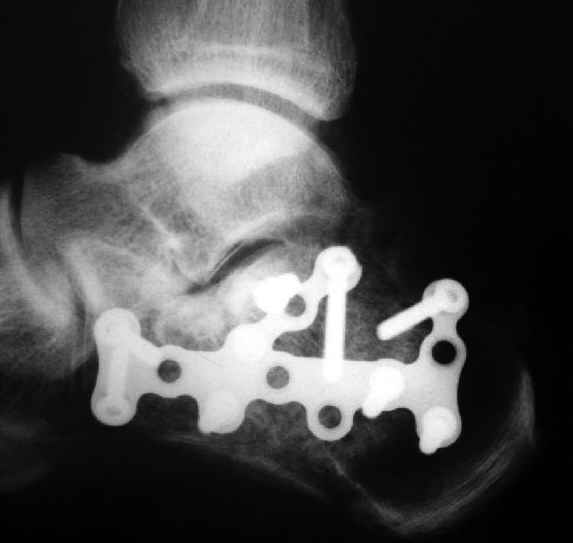

Очень хорошее впечатление осталось после использования выпускаемой для остеосинтеза пяточной кости АО реконструктивной пластины с угловой стабильностью. В России ее продает Синтез Матис.

В/суставные переломы пяточной кости у молодых являются показанием к оперативной коррекции, Большой материал накоплен у д-ра Дрягина (Челябинск). В нашем отделении предпочтение отдаем открытой репозиции, при наличии выраженного отека, фликтен и т.д.

Окончательная фиксация спицами, пяточными пластинами (5) , в последнее время стали применять крючковидные пластины (ДЕОСТ) (6,6a).

представляю снимки пациента с переломом пяточной кости. послеоперационный снимок этапный - по снятии швов спицы удаляю и наладываю циркулярную гипсовую повязку. к сожалению снимки с удаленной скобой представить не могу но поверьте на слово - консолидация полная, коррекция стойкая.

при планировании операции и ее исполнении выполнена костная аутопластика трансплантатом с гребня подвздошной кости причем трансплантат брался фрезой размером несколько болишим чем образованный в результате травмы дефект. скоба в данном случае обеспечивает компрессию между отломками-трансплантатом